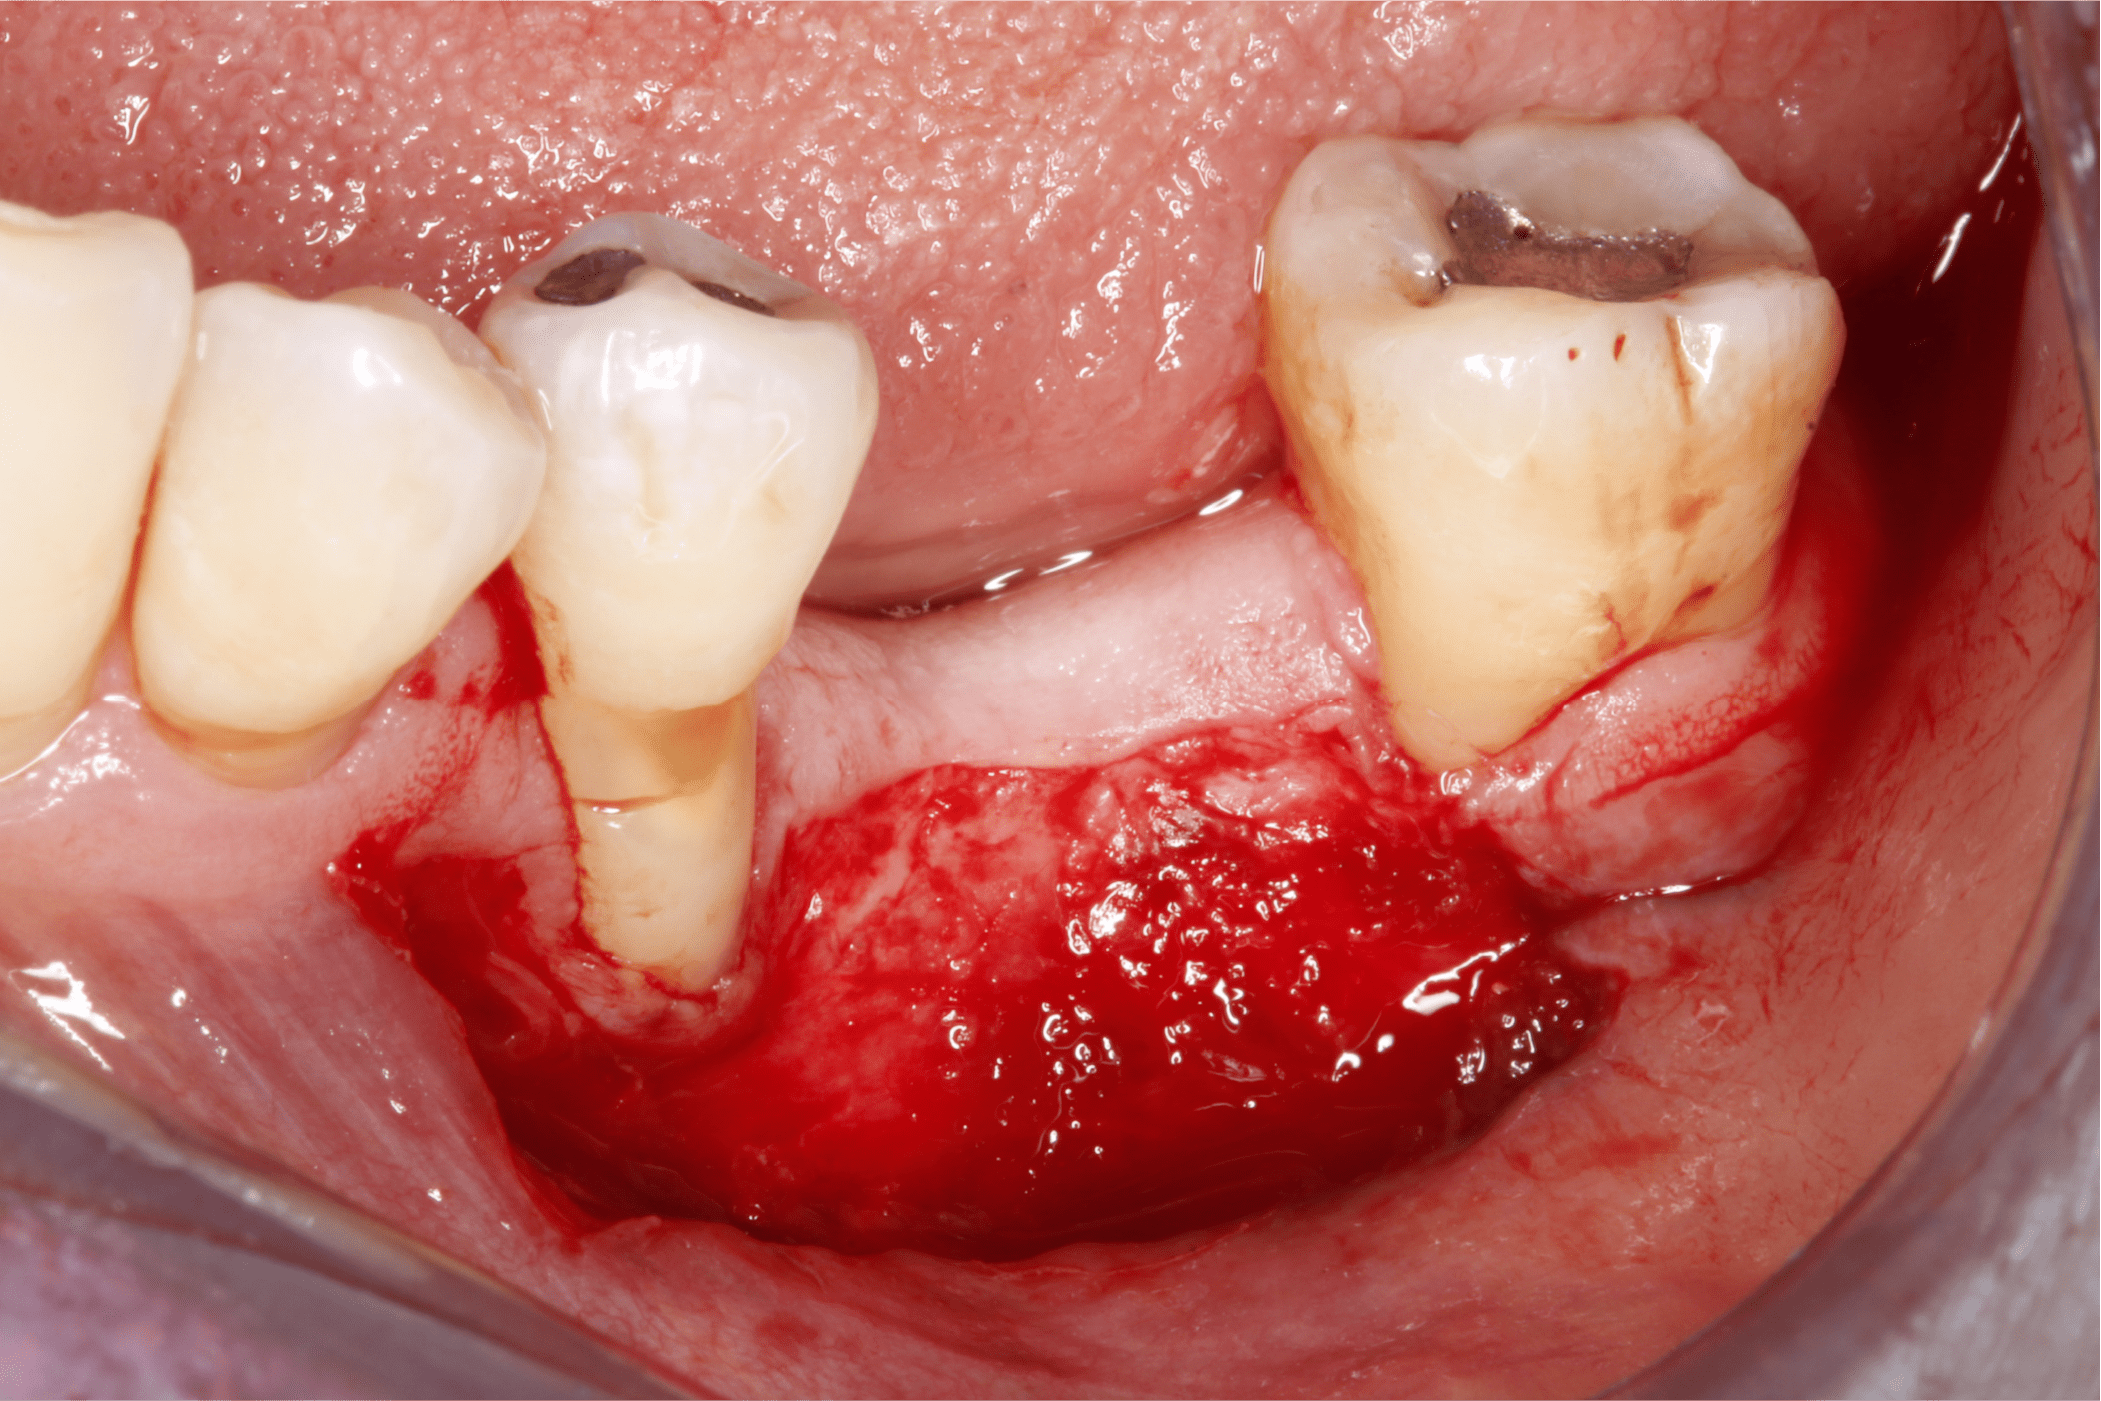

Tras un enjuague antiséptico, se anestesia la zona a tratar y se procede a preparar el lecho receptor por medio de incisiones de espesor parcial dejando periostio expuesto, esto con la intención de darle aporte vascular al injerto. (Fig. 6 y 7).

Fig. 6

Fig. 7